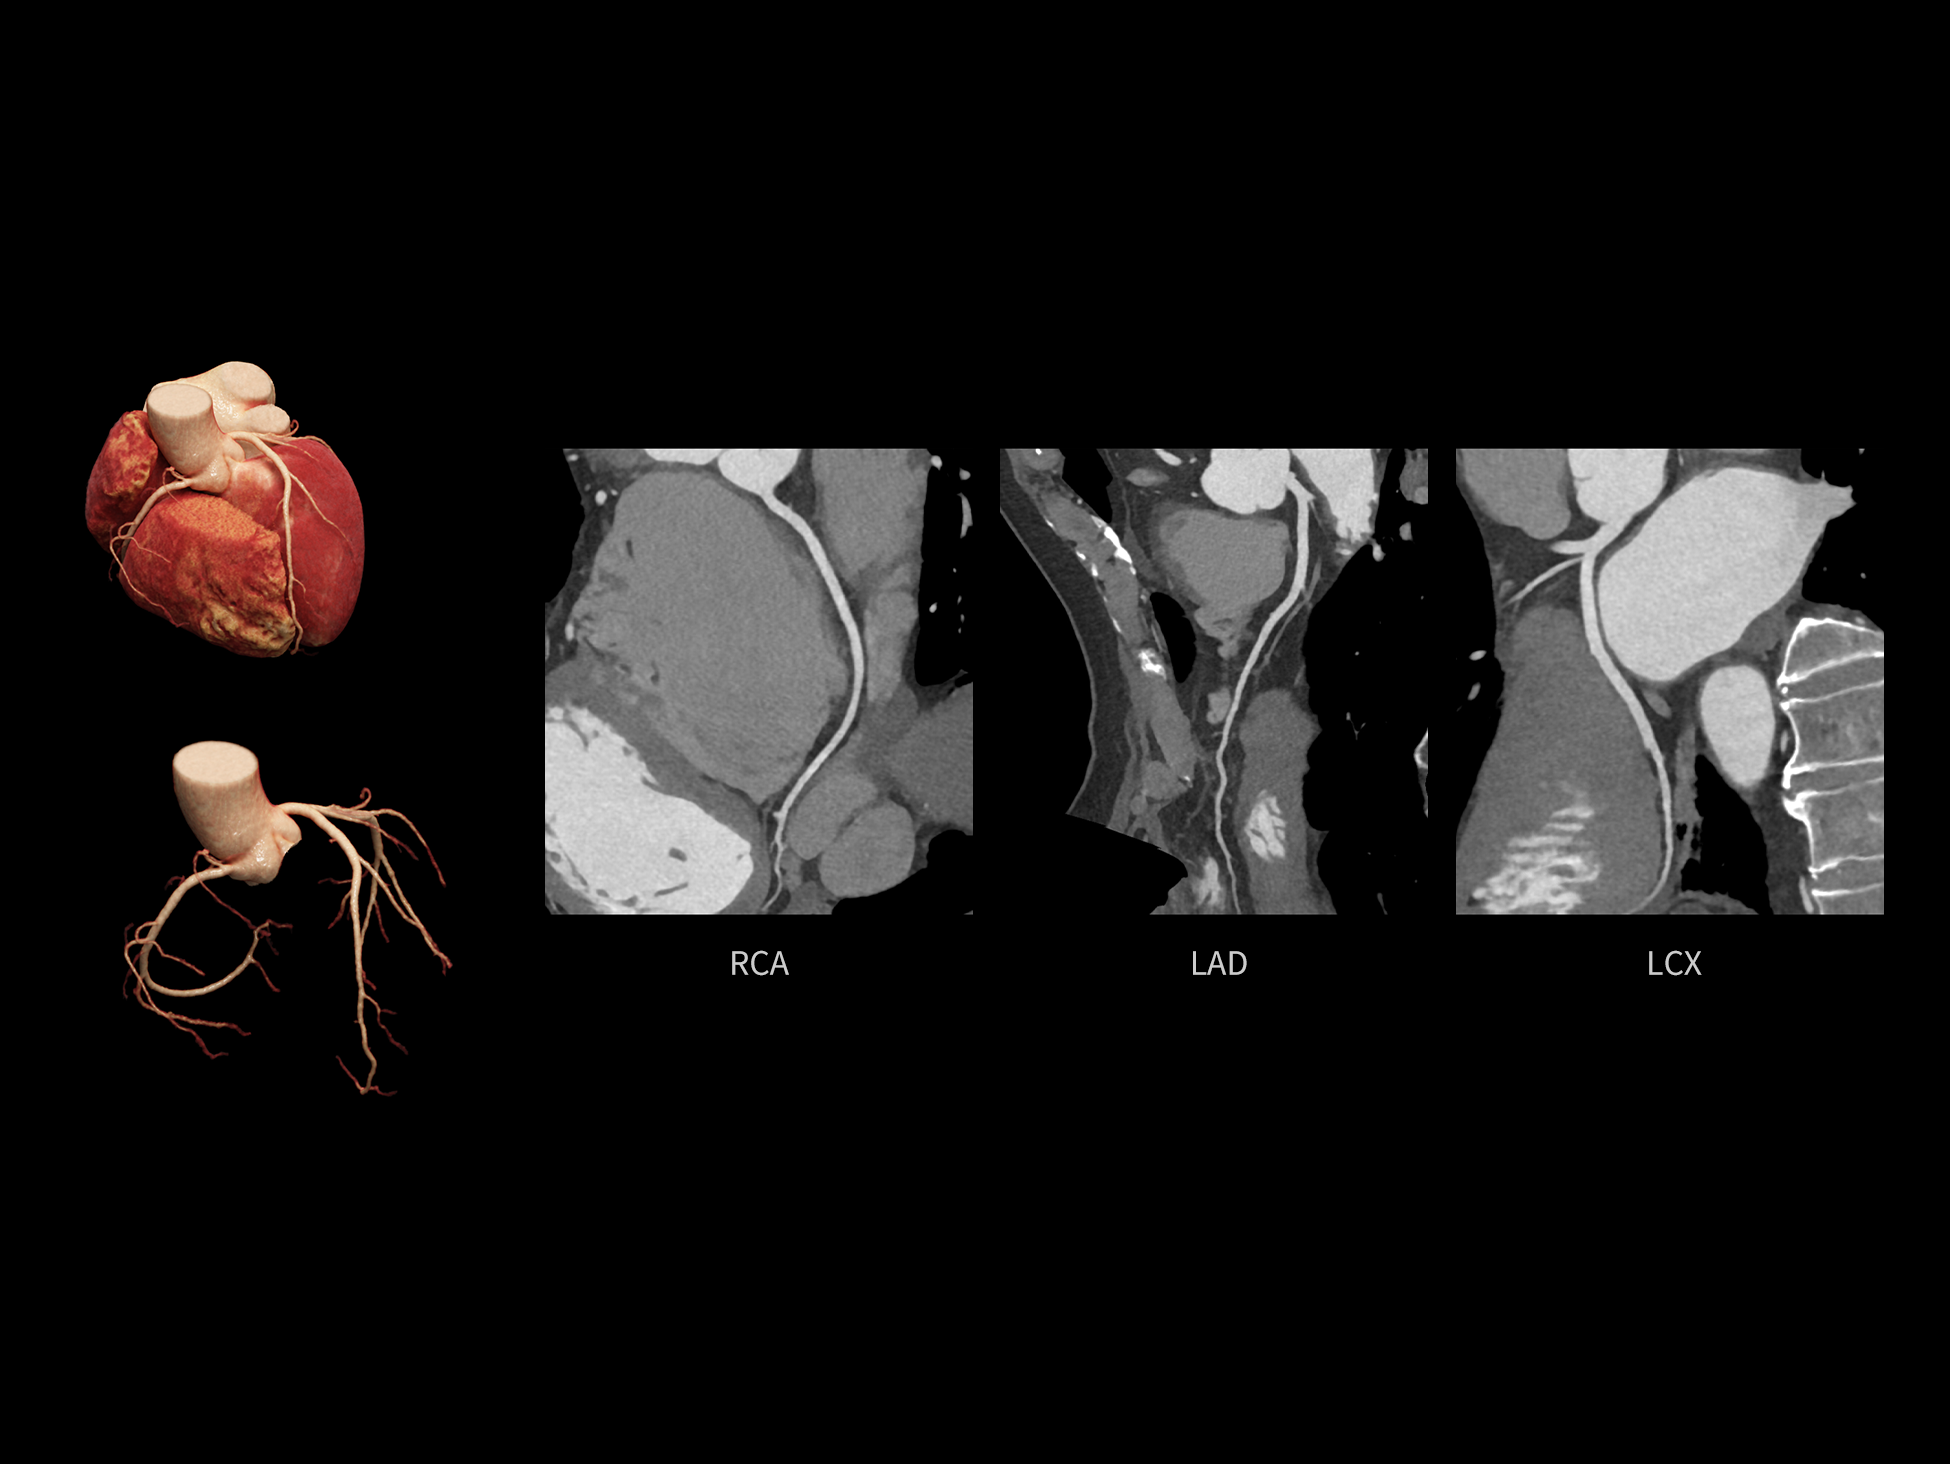

CardioCapture 2.0 通过“识别–追踪–建模–校正”的完整流程,精准分割心脏结构,动态追踪运动轨迹,并构建多时相运动场,最终实现冠脉、瓣膜、心肌及心室结构的同步校正,清晰洞见每一次心跳细微变化,真正将心脏动态掌握于毫秒之间。

CardioCapture 2.0 在目标时相前后重建多时相影像,通过深度学习网络精准提取冠脉中心线,进而建立时相间运动模型,实现对冠脉分段图像的精准运动校正。

CardioCapture 2.0 可对心肌、瓣膜及心室等结构进行同步运动校正。基于深度学习的心脏精细分割,实现了更完整的心脏全局信息提取,能有效抑制全心运动伪影,显著提升心脏细节的清晰度与诊断可靠性。

8ms 全心等效时间分辨率

冠脉运动校正

全心结构运动校正

心脏成像,自由掌控

uCT SiriuX® 以 8ms 全心等效时间分辨率与16cm宽体覆盖,突破传统心脏成像局限,完整呈现搏动中的心脏结构与动态功能;配合无心电门控扫描与智能化工作流,更使心脏检查摆脱心率、配合度与操作复杂度的束缚,实现真正自由从容的成像体验,为临床功能评估提供更深层依据。

全心全时相高清成像

单心动周期内的任意时相获取高质量的冠脉CTA图像,确保稳定的心脏成像效果。